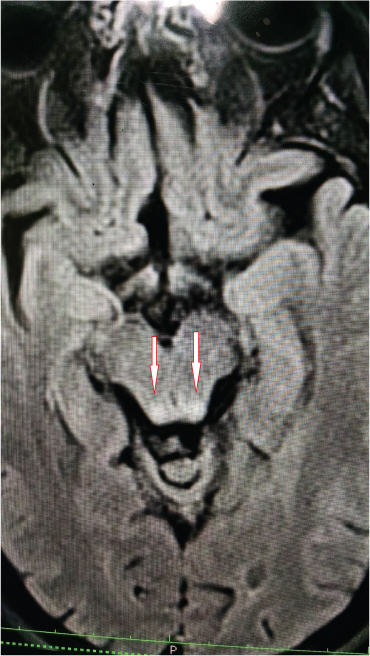

A 45-year-old male patient presented with sudden onset of vertigo, ataxia and slurring of speech since 2 days. The patient was a known case of liver abscess and was treated with percutaneous pigtail catheter drainage elsewhere and oral as well as parenteral antibiotics and was discharged after improvement in symptoms. He was treated with intravenous metronidazole in a dose of 800ml intravenous three times a day for 5 days followed by 800mg orally three times a day for 3 weeks as per his discharge summary. After one month, he came to our hospital with cerebellar symptoms as described above. On examination the patient had staccato speech, restriction of lateral gaze of both eyes and positive cerebellar signs like dysdiadochokinesia and positive Romberg’s sign. The patient was referred to Radiology department for MRI brain which showed symmetrical hyperintensities in bilateral dentate nuclei and tectum on T2W & FLAIR sequences [Table/Fig-1,2, and 3].

FLAIR axial image showing symmetrical hyperintensity in tectum

MRI plays an important role in the diagnosis and follow-up of these cases. Increased signal intensity is observed on T2W/FLAIR sequences [3] as seen in our patient. It may also have a prognostic value in predicting the symptomatic improvement. Since our patient had few lesions without involvement of corpus callosum, he improved within three days of cessation of metronidazole. The typical locations of lesions in metronidazole induced encephalopathy are the cerebellar dentate nuclei, tectum, red nucleus, and tegmentum around periaqueductal gray matter, dorsal pons and medulla and splenium of corpus callosum. The lesions are bilaterally symmetrical [8]. The inferior olivary nucleus and the white matter of the cerebral hemispheres are uncommon locations [10]. Our patient had lesions only in the dentate nuclei bilaterally and tectum. The signal intensity changes observed on the diffusion weighted images most likely represent interstitial oedema except for the splenium of corpus callosum where it could represent cytotoxic oedema [11].